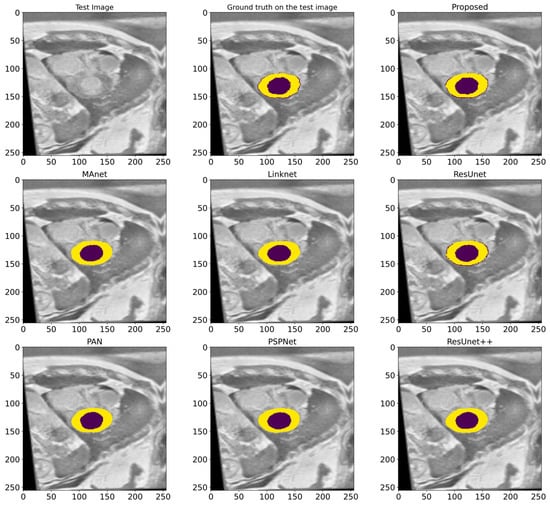

4.4. Comparison with Other State-of-the-Art Models

In this work, a comparative evaluation of the performance of the proposed model with six other SOTA deep segmentation models was carried out to demonstrate its superiority over its analogs. Figure 10 provides a qualitative comparison of segmentation results produced by various models against the ground truth. The proposed model demonstrates the highest visual accuracy, closely aligning with the manual annotations for both the LV and Myo regions. ResUnet also performs well, showing smooth and spatially coherent boundaries, although with slightly less precision than the proposed model. In contrast, models such as PAN, PSPNet, and ResUnet++ tend to over-segment the Myo area, while others like MAnet and LinkNet display a moderate agreement with the ground truth. These visual results support the effectiveness of the proposed architecture in capturing detailed anatomical structures more reliably than existing approaches. Table 2 provides more evaluation metrics, such as the Recall, Dice, precision, and F1-score, that allow for a thorough comparison of the performance of different models. The visualization of these metrics is presented in Figure 11, which enables us to demonstrate their comparison. The analysis of the results showed that the proposed model not only outperforms other modern models in most metrics but also demonstrates stable results on various datasets, which indicates its versatility and reliability. Table 2 shows that our model demonstrates superiority over the best SOTA segmentation model (MAnet []). Specifically, it outperforms MAnet by an IoU of 2.2%, a Recall of 2.88%, a Dice of 1.24%, and an F1-score of 1.24%. These results confirm the high efficiency and accuracy of the proposed model, making it superior not only to MAnet but also to the other six SOTA segmentation models. The very small standard deviation values indicate that our model performs well across all batches and proves the stability of the model’s performance. The results in Table 2 demonstrate the effectiveness of the proposed enhancements, reflecting clear improvements in the segmentation performance. The higher rates of Recall and precision indicate that our model can more effectively identify and classify objects in images and minimize the number of missed objects (false negatives) and misclassified objects (false positives). These findings indicate the value of our study and the development of the proposed approach; moreover, these results confirm the excellence of our model and indicate its potential for applications in various practical contexts where precise segmentation is critical. Therefore, the proposed model can provide a foundation for future research and development in image segmentation.

Figure 10.

A visualized comparison of predictions of different deep segmentation models. The LV is marked in the deep violet color, and the Myo is highlighted in yellow.